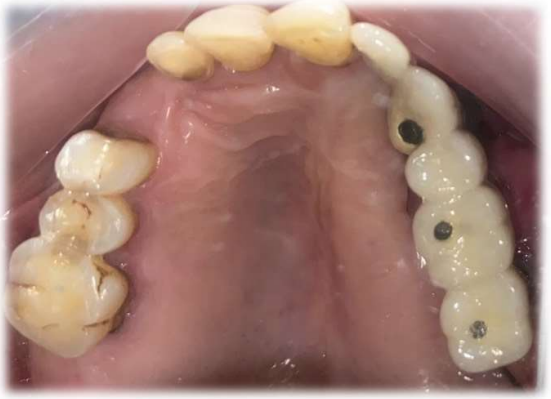

A 55-year-old man was referred to the Department of Prosthodontics with complaints of hypernasal speech, nasal regurgitation, and oroantral communication. He had undergone post Mucormycosis partial maxillectomy (Left Maxilla) and had not received any prosthetic rehabilitation (Figure 1). The patient presented with oroantral communication and difficulty in speech and mastication.

Figure 1: Maxillary defect post Mucormycosis

Figure 1